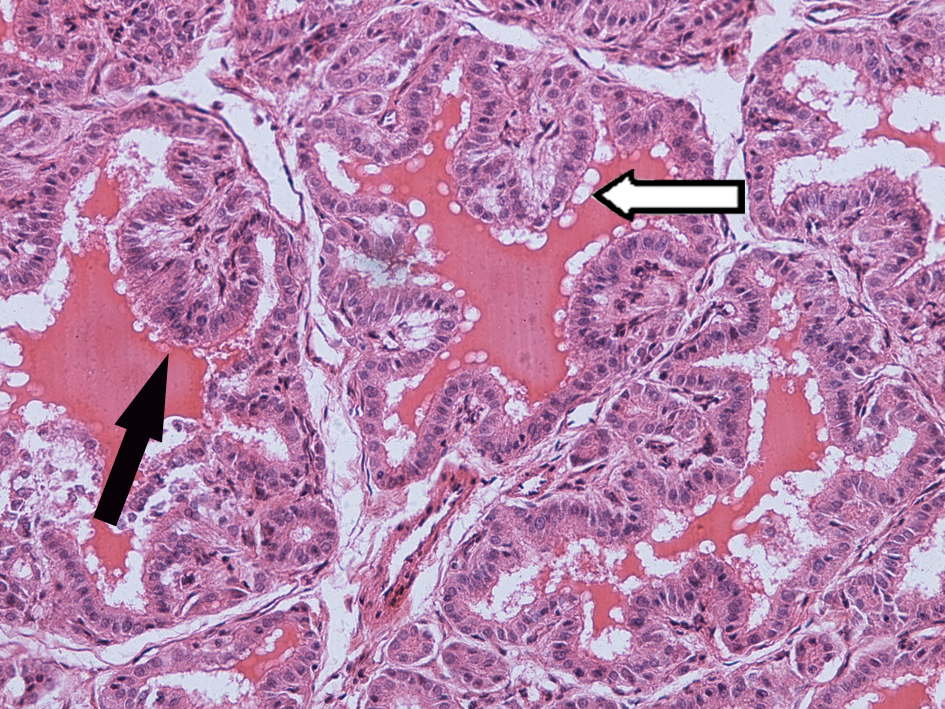

2. Invasive ductal cancer of the breast:

3.Carcinoma in situ of the cervix

1.Graves disease

2.Diabetic nephropathy

1.Epidemic cerebrospinal meningitis (purulent meningitis)

2.Encephalitis type B-liquefied necrosis

2.Encephalitis type B-2

1.Tuberculous lymphadenitis

2.Chronic cavitary tuberculosis of the lung

3.Typhoid fever of intestine

1.Amebic colitis

2.Schistosomiasis of the colon

3.Experimental acute schistosomiasis of the liver (rabbit)

4.Pile-stem liver fibrosis of schistosomiasis